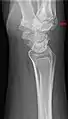

Carpal boss in plain X-Ray.